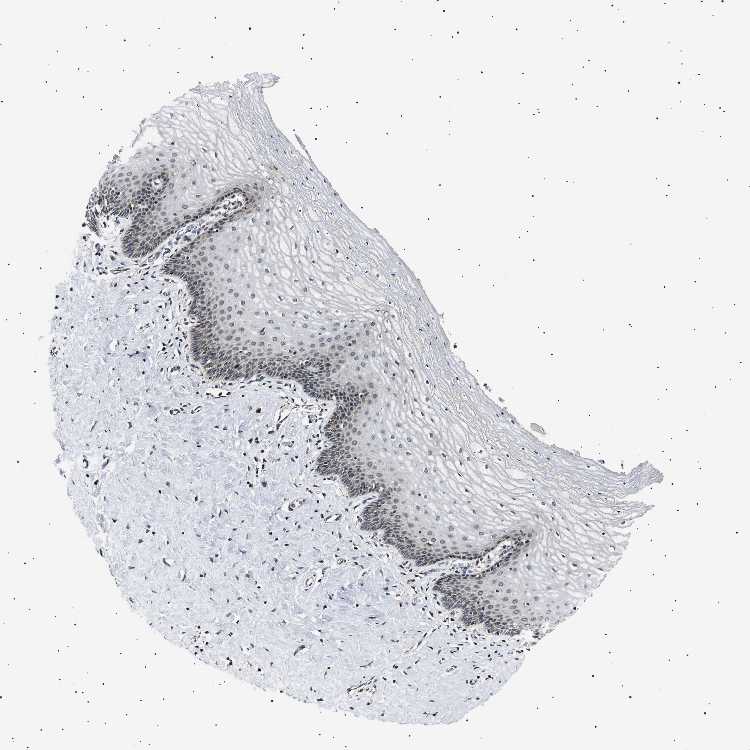

TISSUE PRIMARY DATA CERVIX Show tissue menu

CERVIX - Antibody stainingi

Antibody staining in the annotated cell types in the current human tissue is reported as not detected, low, medium, or high, based on conventional immunohistochemistry profiling in selected tissues. This score is based on the combination of the staining intensity and fraction of stained cells.

Each image is clickable and will lead to virtual microscopy that enables deeper exploration of all samples and also displays staining intensity scores, fraction scores and subcellular localization as well as patient and tissue information for each sample.

Antibody HPA039867Antibody CAB020833

Glandular cells Not detected-

Squamous epithelial cells Not detectedNot detected